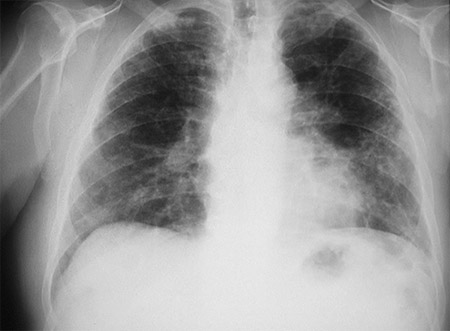

RT de asbestosis

De la colección personal de Kenneth D. Rosenman, Michigan State University